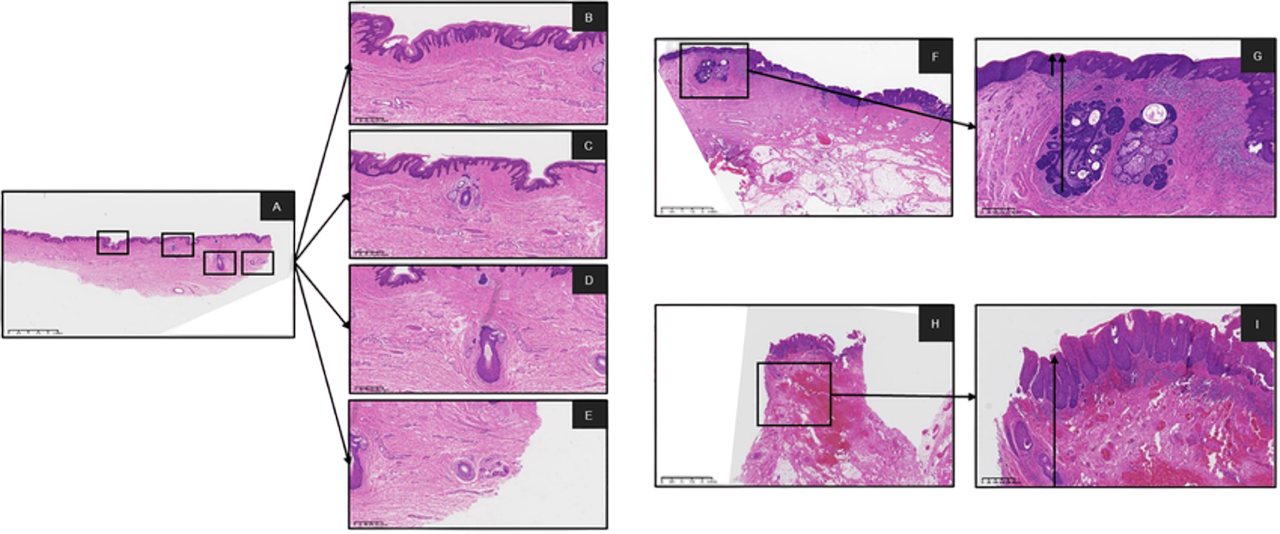

Diagnosticar en una pantalla ofrece múltiples ventajas frente al microscopio. Nuestros visores KFBio SmartView permiten manipular la muestra en alta resolución y en gran formato, con herramientas de zoom, medición y anotación que facilitan el análisis detallado.